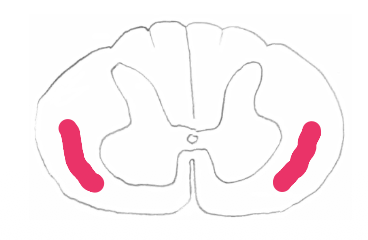

Lateral Spinothalamic Tract

Outline the Lateral Spinothalamic Tract.

1st order neuron (spinal cord)

Cell body: dorsal root ganglion

travels through Lissauer’s tract

ends at substantia gelatinosa

2nd order neuron (spinal cord)

Cell body: Substantia gelatinosa

axon crosses obliquely in anterior white commissure, then ascends in the contralateral white column as the “lateral spinothalamic tract" (bunch of 2er neurons)

spinal cord → brainstem → thalamus

ends in VPL nucleus

For the Lateral Spinothalamic Tract:

Which order neuron is ascending in the white columns?

Which order neuron is ascending in the brainstem?

Which white columns do you find them in and where in the brainstem?

White column = 2nd-order neuron (contralateral white columns)

Brainstem = 2nd-order neuron (spinal lemniscus)